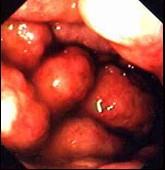

问题 患者,男,16岁,反复发热、消瘦1月,查体:心肺腹无阳性体征。电子胃镜图片如下,诊断为 ( )

选项 A.胃癌 B.胃淋巴瘤 C.胃溃疡 D.胃溃疡并真菌感染 E.克罗恩病

答案 B